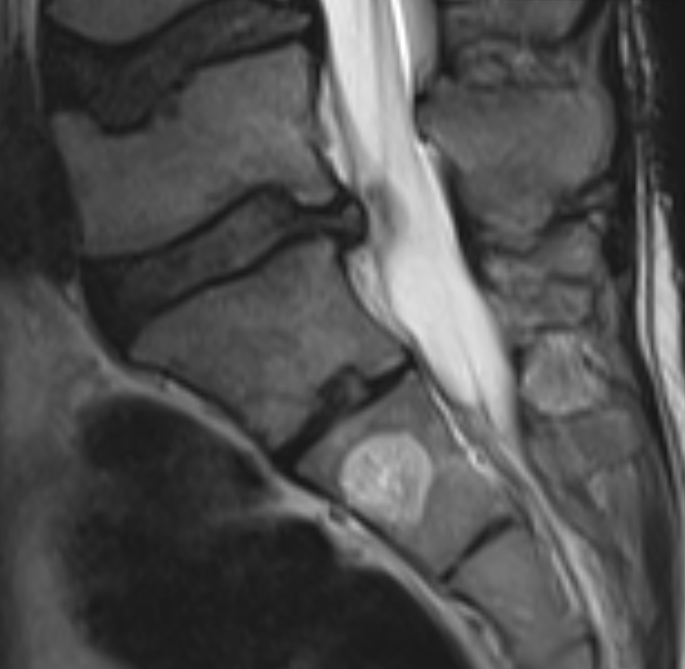

3. Vertebral haemangioma